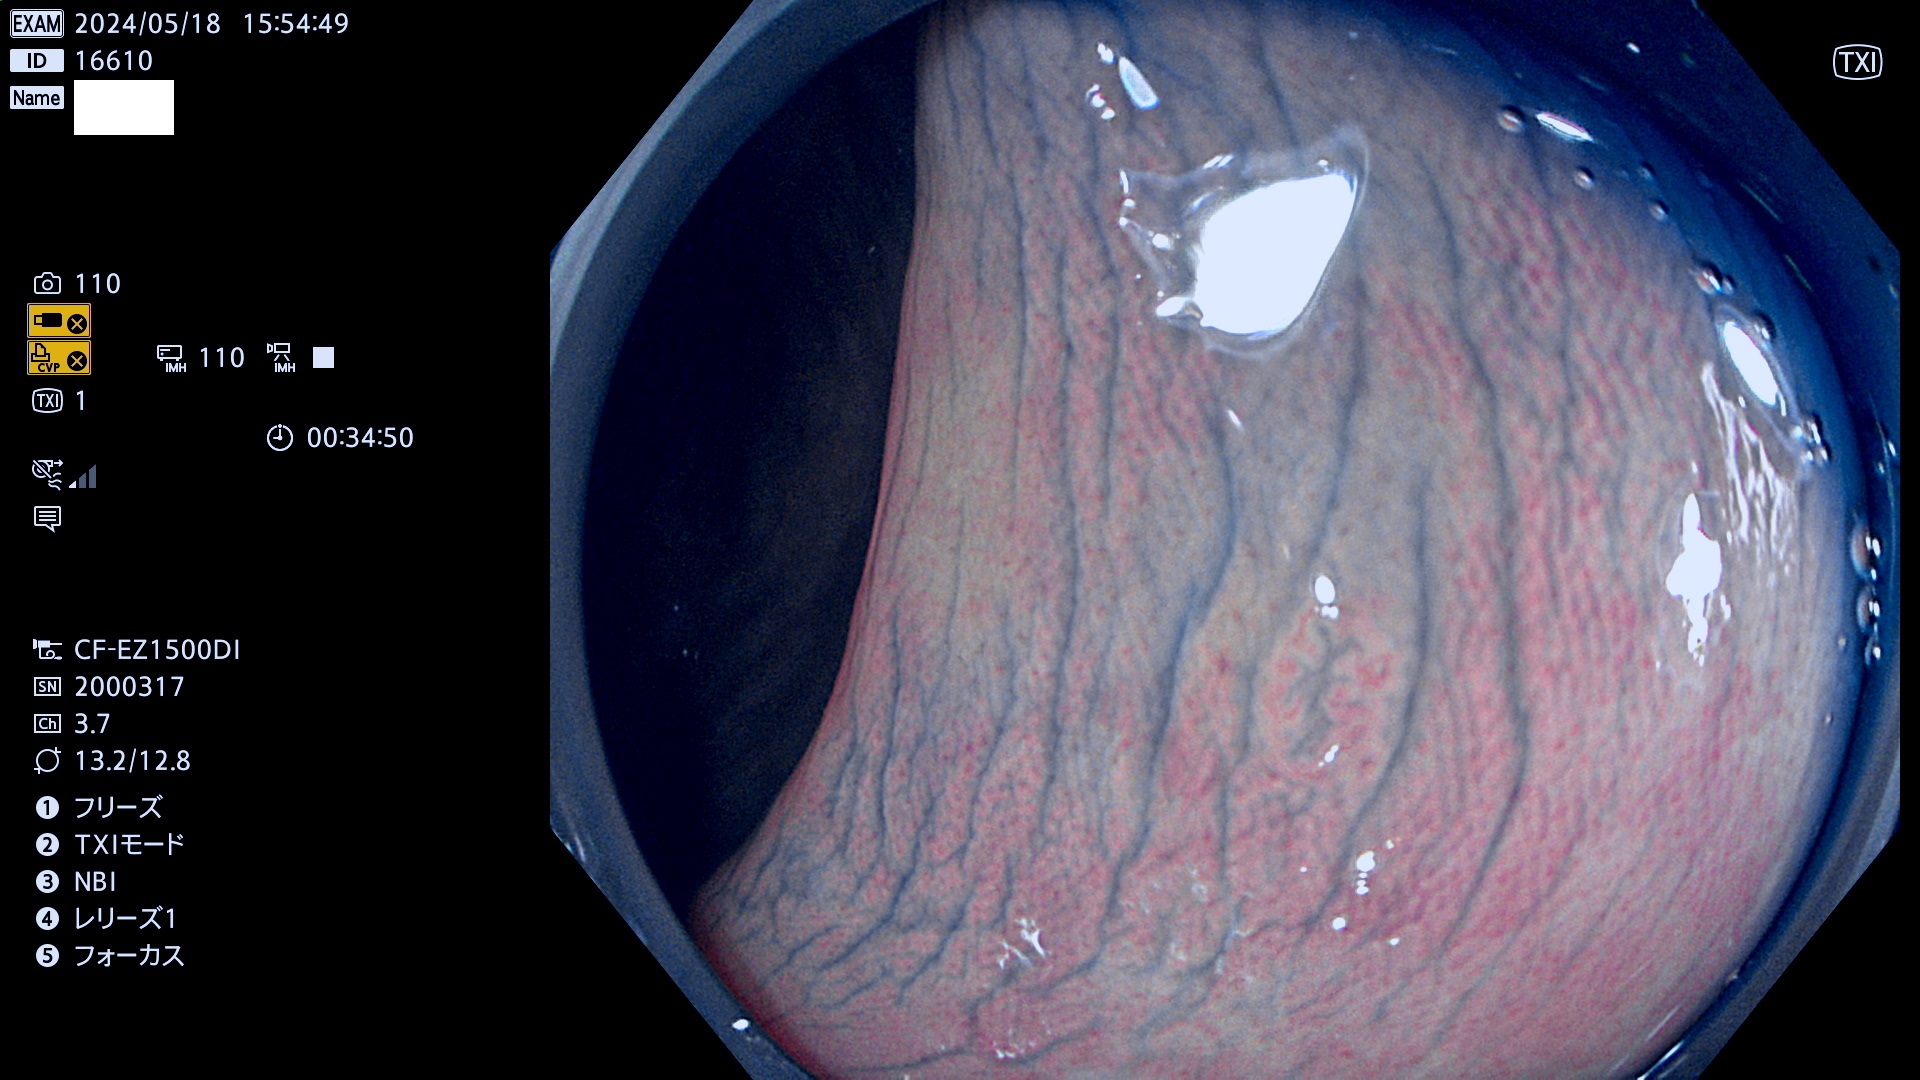

表面型腺腫(Flat Adenoma)の中で、完全に平坦な物をUb、陥凹している物をUcと呼びます。平坦隆起型(Ua)よりも、発見が難しく危険な病変です。

毎週の検査(木・金・土・日)に発見されたUb、Uc型・腺腫を、その週の日曜の夜にUPし1週間、提示します。

抽出の対象期間 2024年5月16日〜5月19の4日間(40件の検査)10件 (10/40=25%)